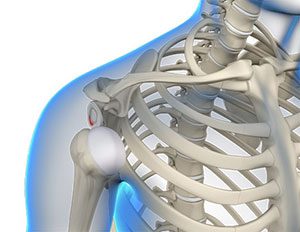

• GPS-guided Shoulder Replacement

Img-GPS-guided Shoulder Replacement

For a successful total shoulder replacement, accurate positioning of the implants is crucial to accomplish...